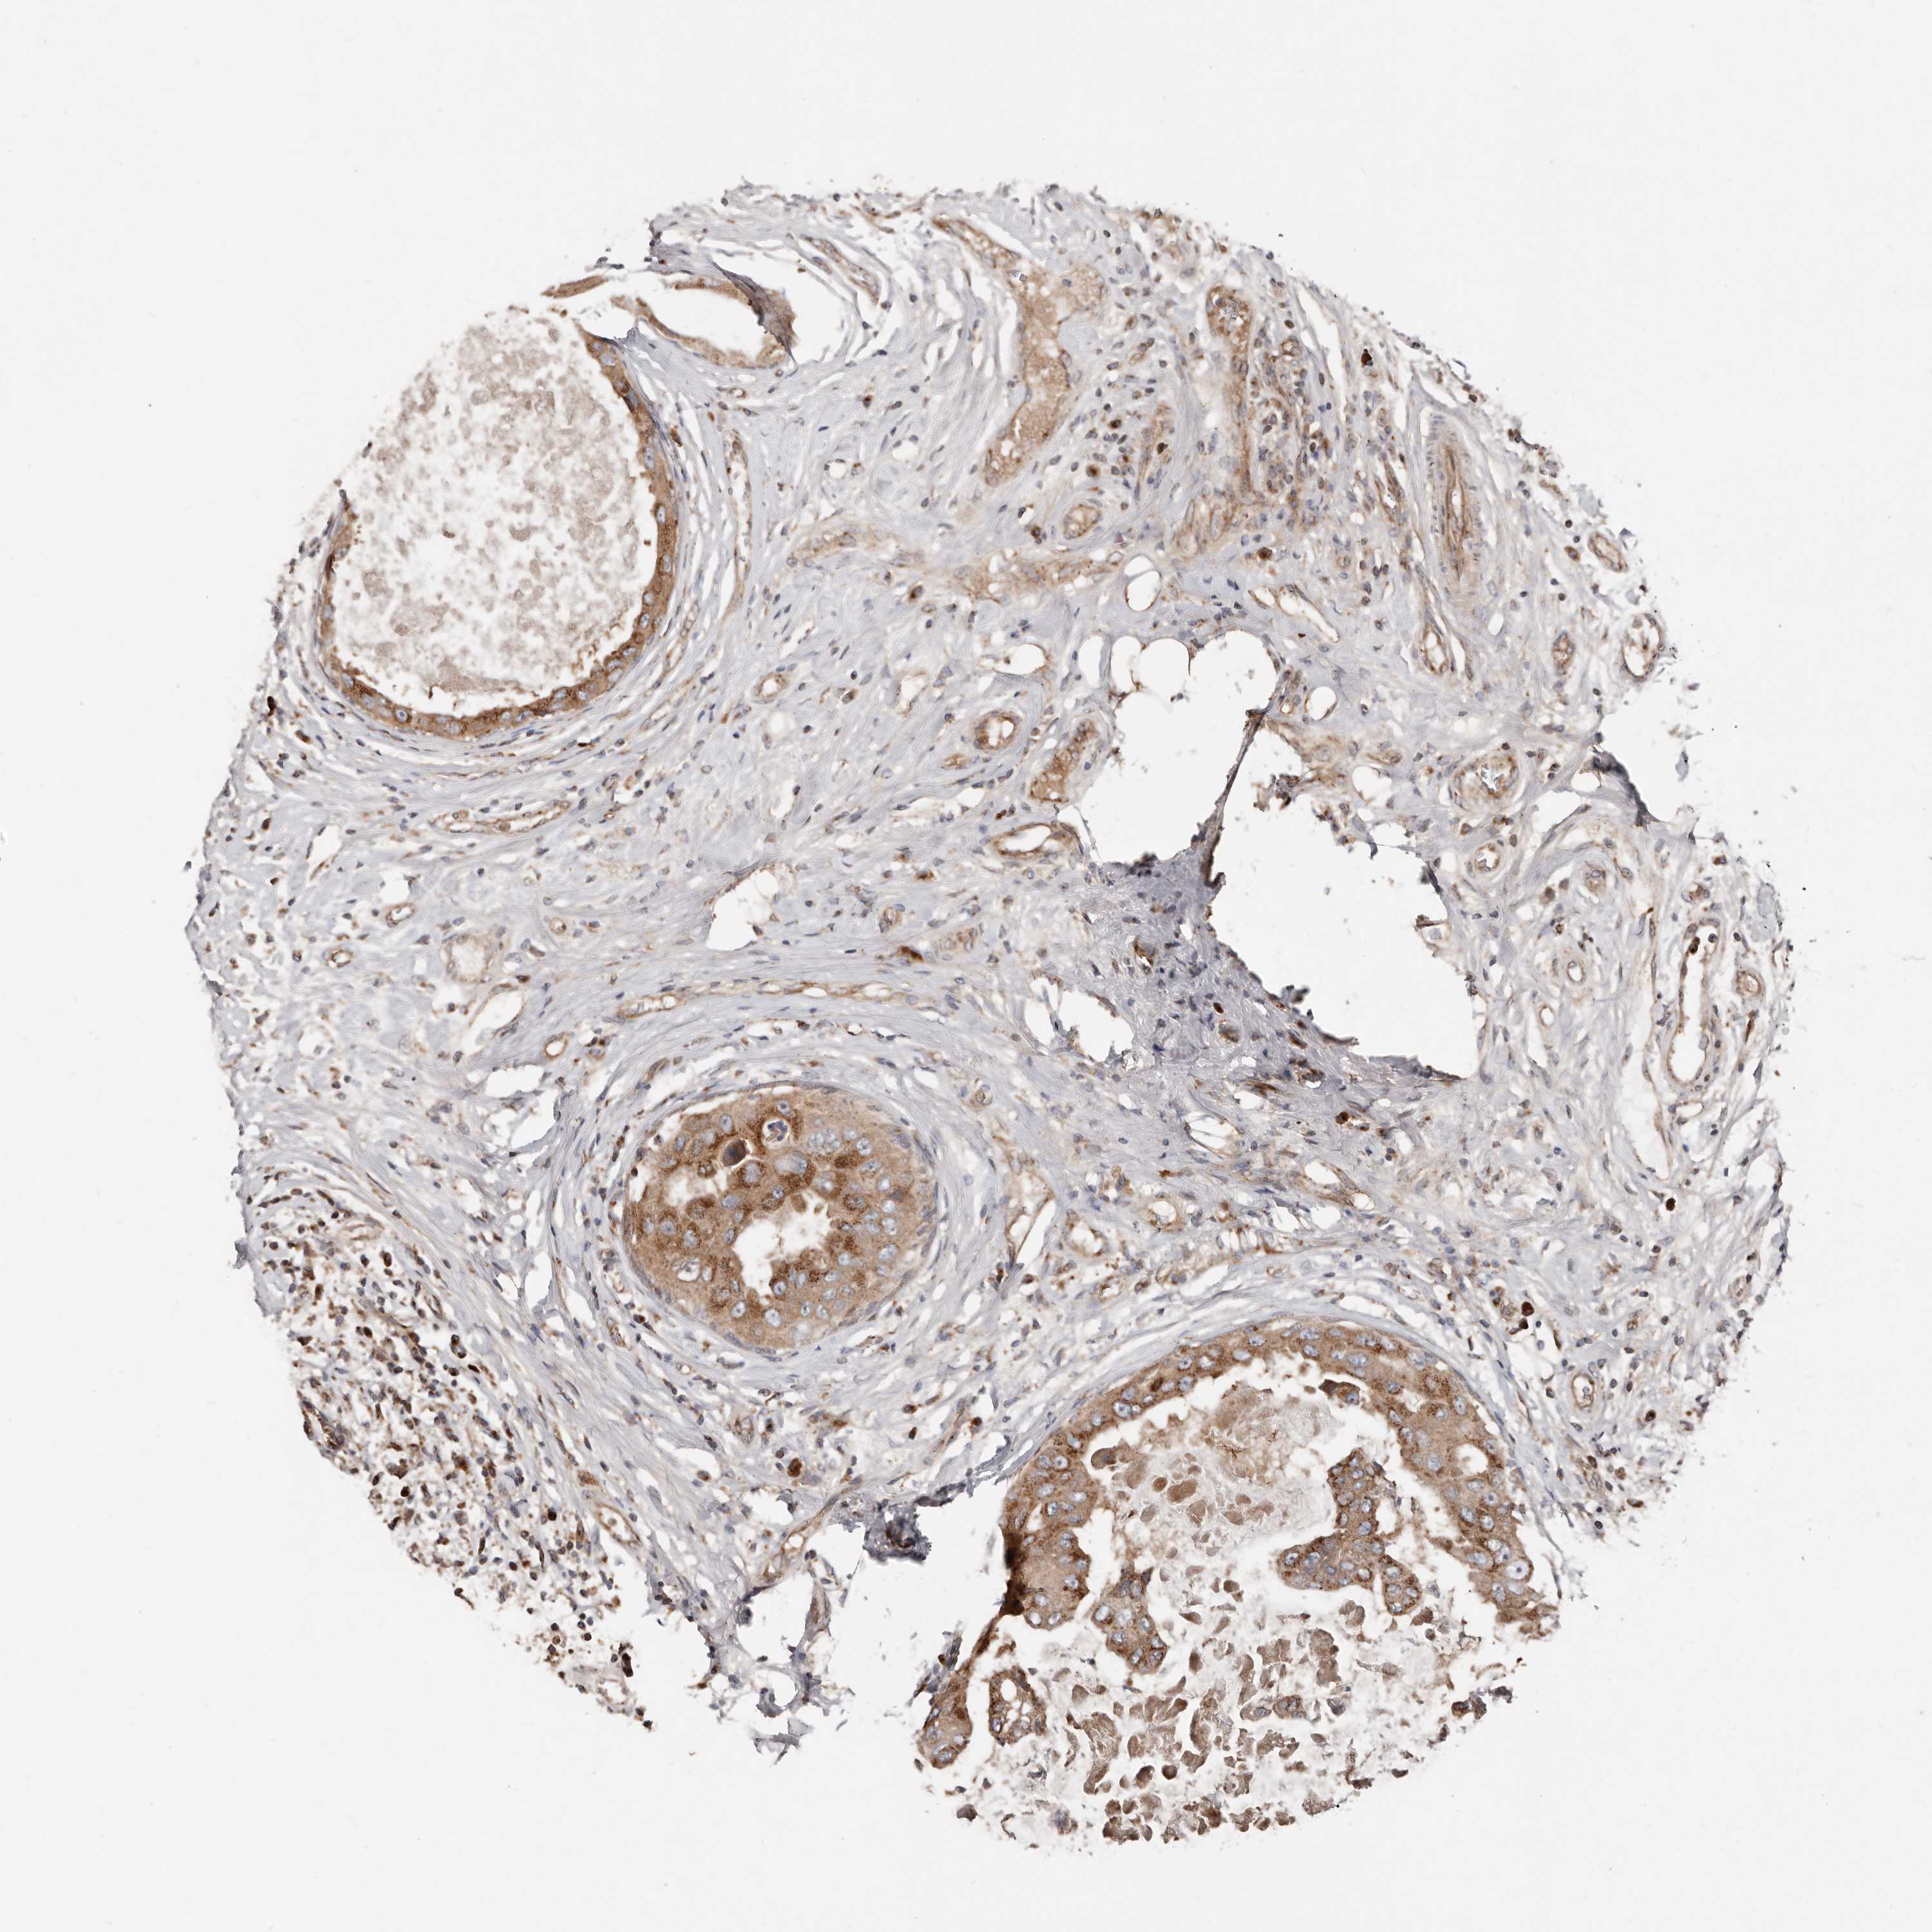

CANCER BREAST CANCER Show tissue menu

BRCA TCGA BRCA VALIDATION PROTEIN EXPRESSION